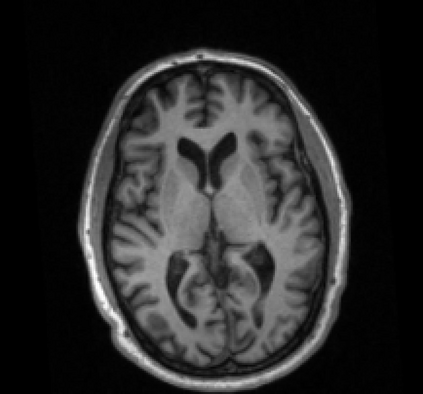

Due to various physical degradation factors and limited counts received, PET image quality needs further improvements. The denoising diffusion probabilistic models (DDPM) are distribution learning-based models, which try to transform a normal distribution into a specific data distribution based on iterative refinements. In this work, we proposed and evaluated different DDPM-based methods for PET image denoising. Under the DDPM framework, one way to perform PET image denoising is to provide the PET image and/or the prior image as the network input. Another way is to supply the prior image as the input with the PET image included in the refinement steps, which can fit for scenarios of different noise levels. 120 18F-FDG datasets and 140 18F-MK-6240 datasets were utilized to evaluate the proposed DDPM-based methods. Quantification show that the DDPM-based frameworks with PET information included can generate better results than the nonlocal mean and Unet-based denoising methods. Adding additional MR prior in the model can help achieve better performance and further reduce the uncertainty during image denoising. Solely relying on MR prior while ignoring the PET information can result in large bias. Regional and surface quantification shows that employing MR prior as the network input while embedding PET image as a data-consistency constraint during inference can achieve the best performance. In summary, DDPM-based PET image denoising is a flexible framework, which can efficiently utilize prior information and achieve better performance than the nonlocal mean and Unet-based denoising methods.